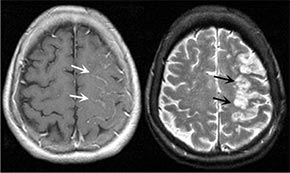

• Poprawić przepływ krwi do mózgu

Brain